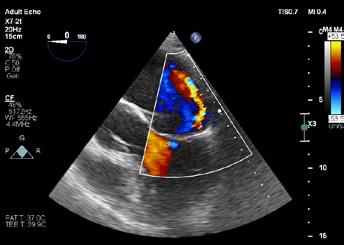

Cazuri disperate în chirurgia cardiacă –atunci când abordul minim invaziv este soluția

Dr. Ion Iovu, Prof. Univ. Dr. Lucian Dorobanțu, Dr. Andreea Bogdan, Dr. Ioana Băjenaru, Dr. Oana Ioniță, Dr. Mădălina Cojocaru, Dr. Toma Iosifescu, Conf. Dr. Cătălin Badiu, Dr. Alexandru Vasilescu